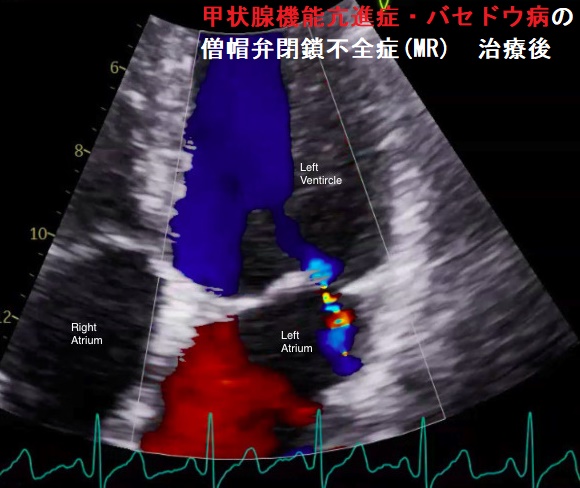

甲状腺機能亢進症/バセドウ病、甲状腺機能低下症/橋本病(下記)

などが原因となります。

甲状腺機能亢進症/バセドウ病、甲状腺機能低下症/橋本病では僧帽弁腱索/乳頭筋断裂の頻度が高い(Endocr Rev. 2005;26(5):704–728.)。

自己免疫性に粘液多糖類が蓄積し、僧帽弁の粘液水腫性変化が生じます

- 甲状腺機能亢進症/バセドウ病の33%

- 甲状腺機能低下症/橋本病の36%

(Thyroid. 2002 Mar; 12(3):193-5.)

特に循環血液量・心拍出量が増加する甲状腺機能亢進症/バセドウ病では、僧帽弁腱索/乳頭筋断裂を引きおこす危険性が高い。(J Endocr Soc. 2018 Sep 17;2(11):1246-1250.)[Endocrinol Diabetes Metab Case Rep. 2022 Jul 1;2022:22-0298.]

僧帽弁腱索/乳頭筋断裂がなく、粘液腫性変性による中等度から重度の僧帽弁閉鎖不全症(MR)なら、甲状腺機能の正常化に伴い改善する可能性があります。[BMJ Case Rep. 2021 Feb 4;14(2):e239626.]